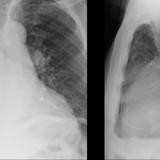

Aortic aneurysm withl ateral

Date: 03/02/2014

Views: 2191